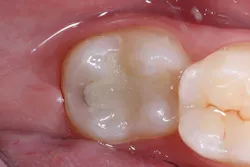

The selective etching technique was chosen, and 37% phosphoric acid (Total Etch, Ivoclar Vivadent) was applied for 30 seconds. The tooth was irrigated with water spray and air-dried (figure 2). Next, a universal bonding agent (Adhese Universal, Ivoclar Vivadent) was scrubbed on the cavity surface until an immobile layer was achieved (figure 3). The excess solvent was removed with an air stream for 20 seconds, and the adhesive was light cured for 10 seconds with an LED light (Bluephase Style, Ivoclar Vivadent) 1 mm away from the cavity.